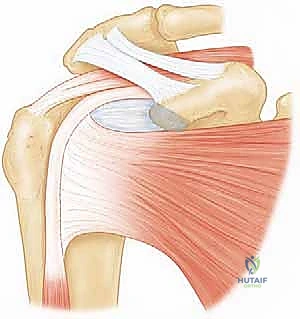

2. الكفة المدورة (Rotator Cuff) والعضلة تحت الكتف

الكفة المدورة هي مجموعة من أربع عضلات تغلف رأس عظم العضد لتثبيته في مكانه وتوجيه حركته. العضلات الأربع هي: فوق الشوكة، تحت الشوكة، المدورة الصغيرة، والعضلة تحت الكتف (Subscapularis).

العضلة تحت الكتف هي الأكبر والأقوى بين هذه العضلات الأربع. تنشأ من السطح الأمامي للوح الكتف (الحفرة تحت الكتف) وتلتصق بالحديبة الصغيرة لعظم العضد.

* وظيفتها: هي المسؤولة الأساسية عن الدوران الداخلي للذراع (مثل حركة وضع اليد خلف الظهر أو على البطن)، وتلعب دوراً حيوياً في منع خلع الكتف للأمام.

3. وتر العضلة ذات الرأسين الطويل (Long Head of Biceps Tendon)

العضلة ذات الرأسين في مقدمة الذراع لها وتران في الأعلى. الوتر "الطويل" يمر عبر شق في عظم العضد (الثلم بين الحديبتين) ويدخل إلى مفصل الكتف ليلتصق بأعلى تجويف الحق. هذا الوتر يعمل كمثبت إضافي للكتف، ولكنه عرضة للالتهاب والتمزق، خاصة إذا كانت العضلة تحت الكتف المجاورة له ممزقة.

4. الخطوة الثانية: التعامل مع وتر العضلة ذات الرأسين (Biceps Tenodesis)

في معظم حالات تمزق العضلة تحت الكتف، يكون وتر العضلة ذات الرأسين تالفاً أو مخلوعاً من مساره. تركه كما هو سيسبب ألماً مزمناً.

* القطع (Tenotomy): يتم قطع الوتر من منشئه التالف داخل المفصل.

* التثبيت (Tenodesis): يتم إعادة تثبيت الجزء السليم من الوتر في عظم العضد (خارج مفصل الكتف الرئيسي) باستخدام خطافات معدنية أو بلاستيكية متقدمة. هذا الإجراء يزيل الألم تماماً ويحافظ على شكل وقوة العضلة ذات الرأسين في الذراع.